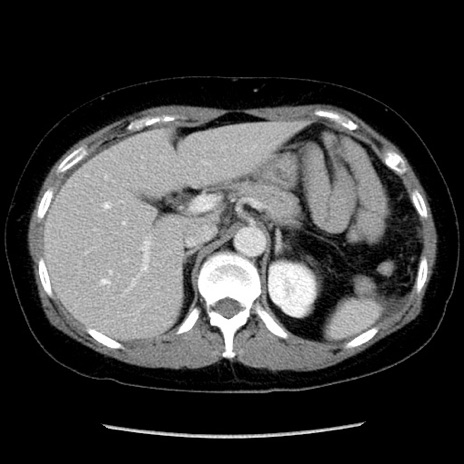

症例6(横断像)

【症例】50歳代女性

【主訴】下腹部痛

【現病歴】本日朝より下痢2回あり。 昼食を食べた後、嘔吐3回、下腹部痛認め、症状軽快せず、当院救急搬送。

最終食事:本日昼(生ものなし)。 昨日の夜、刺身を食ぺたとのこと。周囲に同様の症状の者なし。普段、排便は毎日あるとのこと。

【既往歴】卵巣癌術後(8年前に当院で卵巣摘出)

【身体所見】 意識清明、腹部:平坦、腸蠕動音→、やや硬、下腹部自発痛・圧痛あり、反跳痛あり、筋性防御なし。

【データ】WBC 16000、CRP 0.01